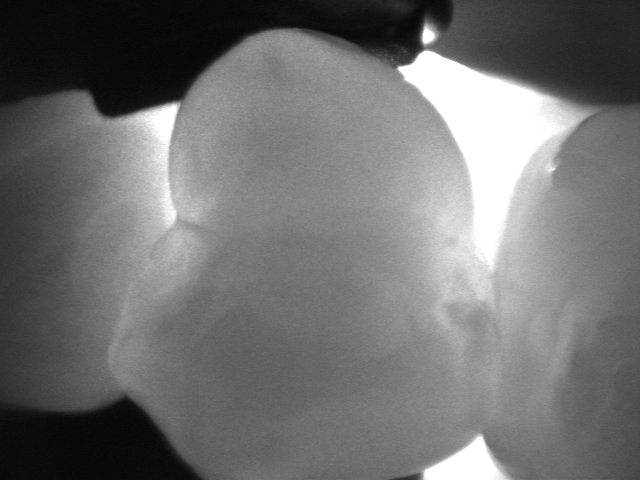

La videocamera digitale sulla testa del manipolo rileva luci ed ombre all’interno del dente e proietta l’immagine ottenuta sullo schermo del pc in tempo reale: le parti sane, che consentono il passaggio della luce, risultano chiare, quelle lesionate, che al contrario lo bloccano, si distinguono nettamente come aree scure.

Le immagini in bianco e nero, altamente dettagliate, ricordano molto le radiografie ma di fatto sono state del tutto ottenute senza radiazioni, soltanto per transilluminazione laser!

Vedere l’estensione della lesione, se ancora soltanto sullo smalto o già sconfinata in dentina, e la sua esatta posizione sono informazioni fondamentali per impostare una terapia che sia il più possibile conservativa.

I fermo immagine ottenuti servono a motivare il paziente e rendere più comprensibile il piano di trattamento. Nel caso di lesioni iniziali permettono, inoltre, un attento monitoraggio nel tempo, ad ogni successivo controllo.

Consente la diagnosi precoce di cracks (incrinature, fratture), demineralizzazioni e carie (occlusale, prossimale o secondaria sotto vecchi restauri), quando sono sopragengivali.

Evidenzia la carie con più sensibilità e attendibilità della sola ispezione visiva e molto prima che appaia alle radiografie, rendendo possibili trattamenti profilattici o minimamente invasivi.